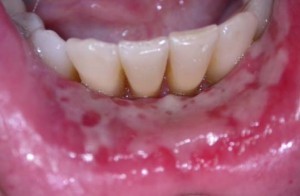

More Extensive Major Ulcerations

Major Aphthous Stomatitis: this more severe form affects approximately 15% of patients with canker sores. These sores often last two weeks or more and are typically over 1 centimeter in diameter. They can be extremely painful and often heal with scarring.